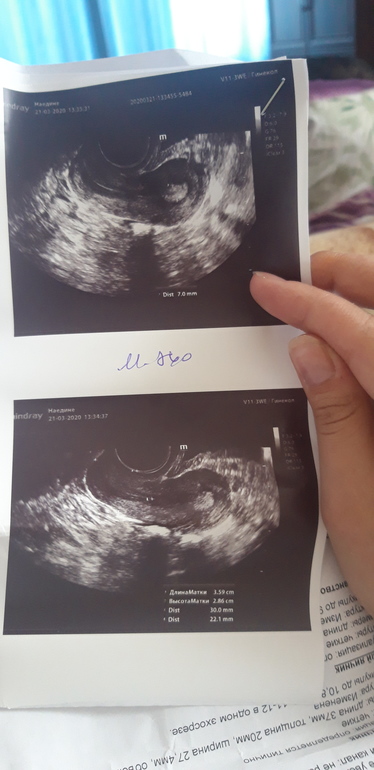

Если не видно, эндометрий 7 мм, возможно желтое тело 20мм